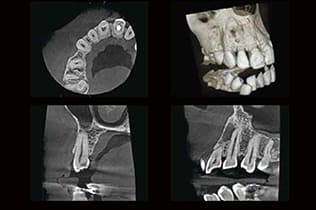

CT・レントゲン撮影

CT検査